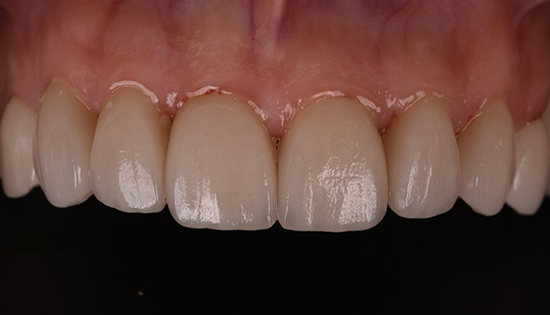

يلجأ الشخص إلى تحسين شكل أسنانه عن طريق فينير الأسنان أو ما يطلق عليه (عدسات الأسنان اللاصقة) وهي عبارة قشرة رقيقه يتم لصقها على السطح الخارجي للأسنان مصنوعة من مواد صلبة ذات معامل شفافيه مطابق للأسنان الطبيعيه   لعلاج مشكلة الاصفرار أو عدم التساوي والعديد من المشاكل الأخرى، حتى يحصل الشخص على ابتسامة رائعة تشبه ابتسامة نجوم هوليود.

• إظهار الأسنان بشكل أكثر جمالًا بعد تغطية كل عيوب الاسنان.

• المواد التي تصنع منها الفينير لا تسبب التهابات وتتقبلها اللثة.

• يحتفظ الفينيرز بلونه وخصائصه لأعوام عديده.